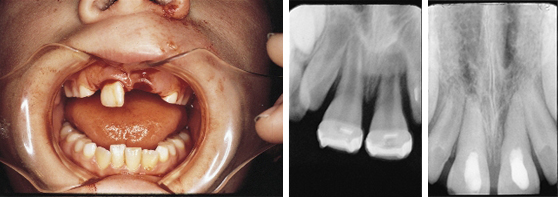

Treatment of Avulsed Tooth

This child presented with avulsed left central and traumatized right central incisors. Two weeks after replantation and splinting, the pulps were removed and Pulpdent Paste was placed in the root canals. The case was followed regularly for 12 months, and the Pulpdent Paste was changed at each visit. After one year, the root canals were obturated with Pulpdent Root Canal Sealer using the Pressure Syringe technique.

Fig. 1: Photo shows child with avulsed left central and traumatized right central incisor.

Fig. 2: Radiograph taken two weeks following replantation shows replanted tooth, open apices and bone loss. At this visit the root canals were negotiated and Pulpdent Paste was placed as a dressing to stimulate healing and discourage traumatic rejection (not shown).

Fig. 3: Radiograph taken one year after treatment shows Pulpdent Paste in the root canals, apexification and bone fill.